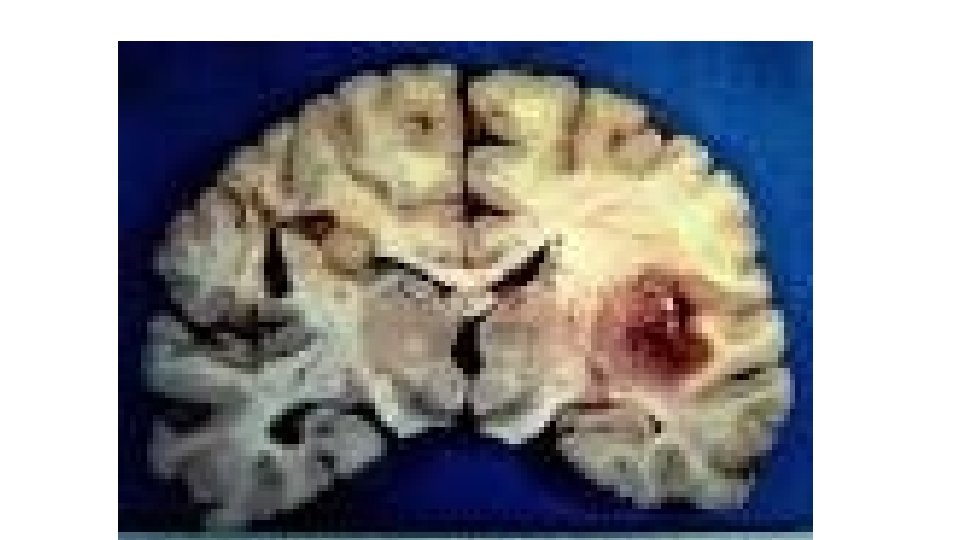

Case II • A 24 year old patient presented to the emergency unit complaining from headache, low grade fever and vomiting for 3 weeks, on examination mild neck stiffness was found. CSF exam showed protein 240 mg/dl, normal sugar and 200 cells: 40% Neutrophils and 60% Lymphocytes. • MRI showed:

• What is the most likely diagnosis? • The patient was treated, discharged home on steroids and anti-TB medications. • Three weeks later: Sever Headache, Vomiting, Weakness and Blurring of vision. • ?